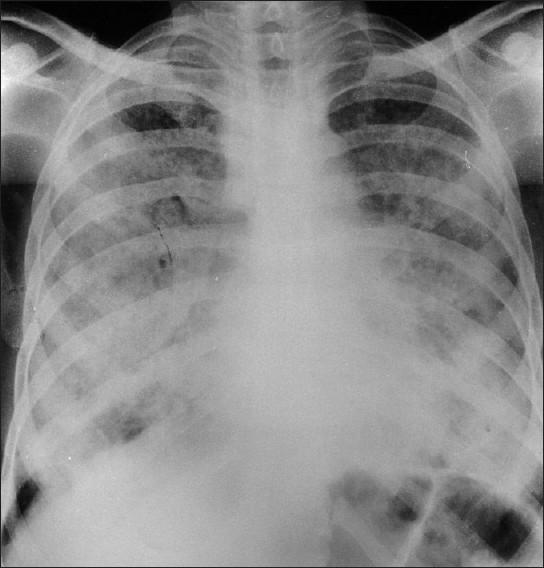

Secondary pulmonary alveolar proteinosis (PAP) is rare but may occur in association with malignancy, certain infections, and exposure to inorganic or organic dust and some toxic fumes. This case report describes the second recorded case of PAP due to exposure to cotton dust. A 24-year-old man developed PAP after working as a spinner for eight years without respiratory protection. He was admitted as an emergency patient with very severe dyspnea for four months and cough for several years. Chest X-ray showed bilateral diffuse alveolar consolidation. He died 16 days later, and a diagnosis of acute pulmonary alveolar proteinosis was made at autopsy. The histopathology demonstrated alveoli and respiratory bronchioles filled with characteristic periodic acid Schiff-positive material, which also revealed birefringent bodies of cotton dust under polarized light. Secondary PAP can be fatal and present with acute respiratory failure. The occupational history and characteristic pathology can alert clinicians to the diagnosis.

继发性肺泡蛋白沉积症(PAP)较为罕见,但可能与恶性肿瘤、某些感染、接触无机或有机粉尘以及一些有毒烟雾有关。本病例报告描述了因接触棉尘导致的第二例有记录的PAP病例。一名24岁男性在未采取呼吸防护措施的情况下担任纺纱工8年后患上了PAP。他因极度严重的呼吸困难持续4个月且咳嗽数年而作为急诊患者入院。胸部X线显示双侧弥漫性肺泡实变。他于16天后死亡,尸检诊断为急性肺泡蛋白沉积症。组织病理学显示肺泡和呼吸性细支气管充满特征性的过碘酸希夫染色阳性物质,在偏振光下还可见棉尘的双折射体。继发性PAP可能致命,并表现为急性呼吸衰竭。职业病史和特征性病理可提醒临床医生做出诊断。